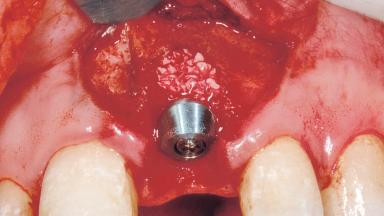

Immediate Placement of an Implant in a Maxillary Left Central Incisor Site

A 33-year-old female patient presented with an upper left central incisor that required extraction after a failed endodontic therapy. The tooth had been traumatized when the patient was a teenager and had undergone several endodontic treatments, including two apicectomy procedures. The patient was in good health and did not smoke. Clinical examination showed that the patient had a high lip line. In full smile, the gingival margins of the upper teeth were visible to the first molars. The gingival margins of central incisors 11 and 21 were only just showing. Examination of tooth 21 confirmed that the tooth was mobile and had hypererupted by 1 mm.